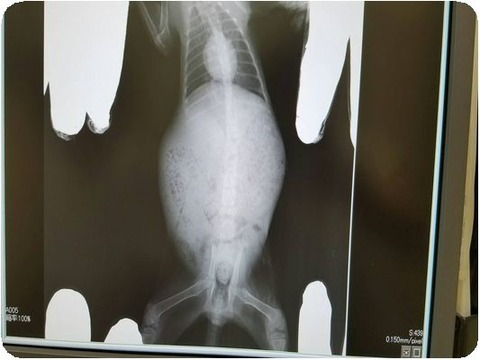

ご協力してくださった方へ

ご覧の通り

負傷子猫の

お腹の中は糞魂でいっぱい

このままだと

一両日中には

ごはんが食べられなくなり

あっという間に

弱っていき

死ぬとこでした。

下半身不随の原因は

骨盤骨折だと

思っていましたが

送られてきた

レントゲンを見る限り

神経損傷ですかね

。。。。。。。。。。。。。。。。。。。。